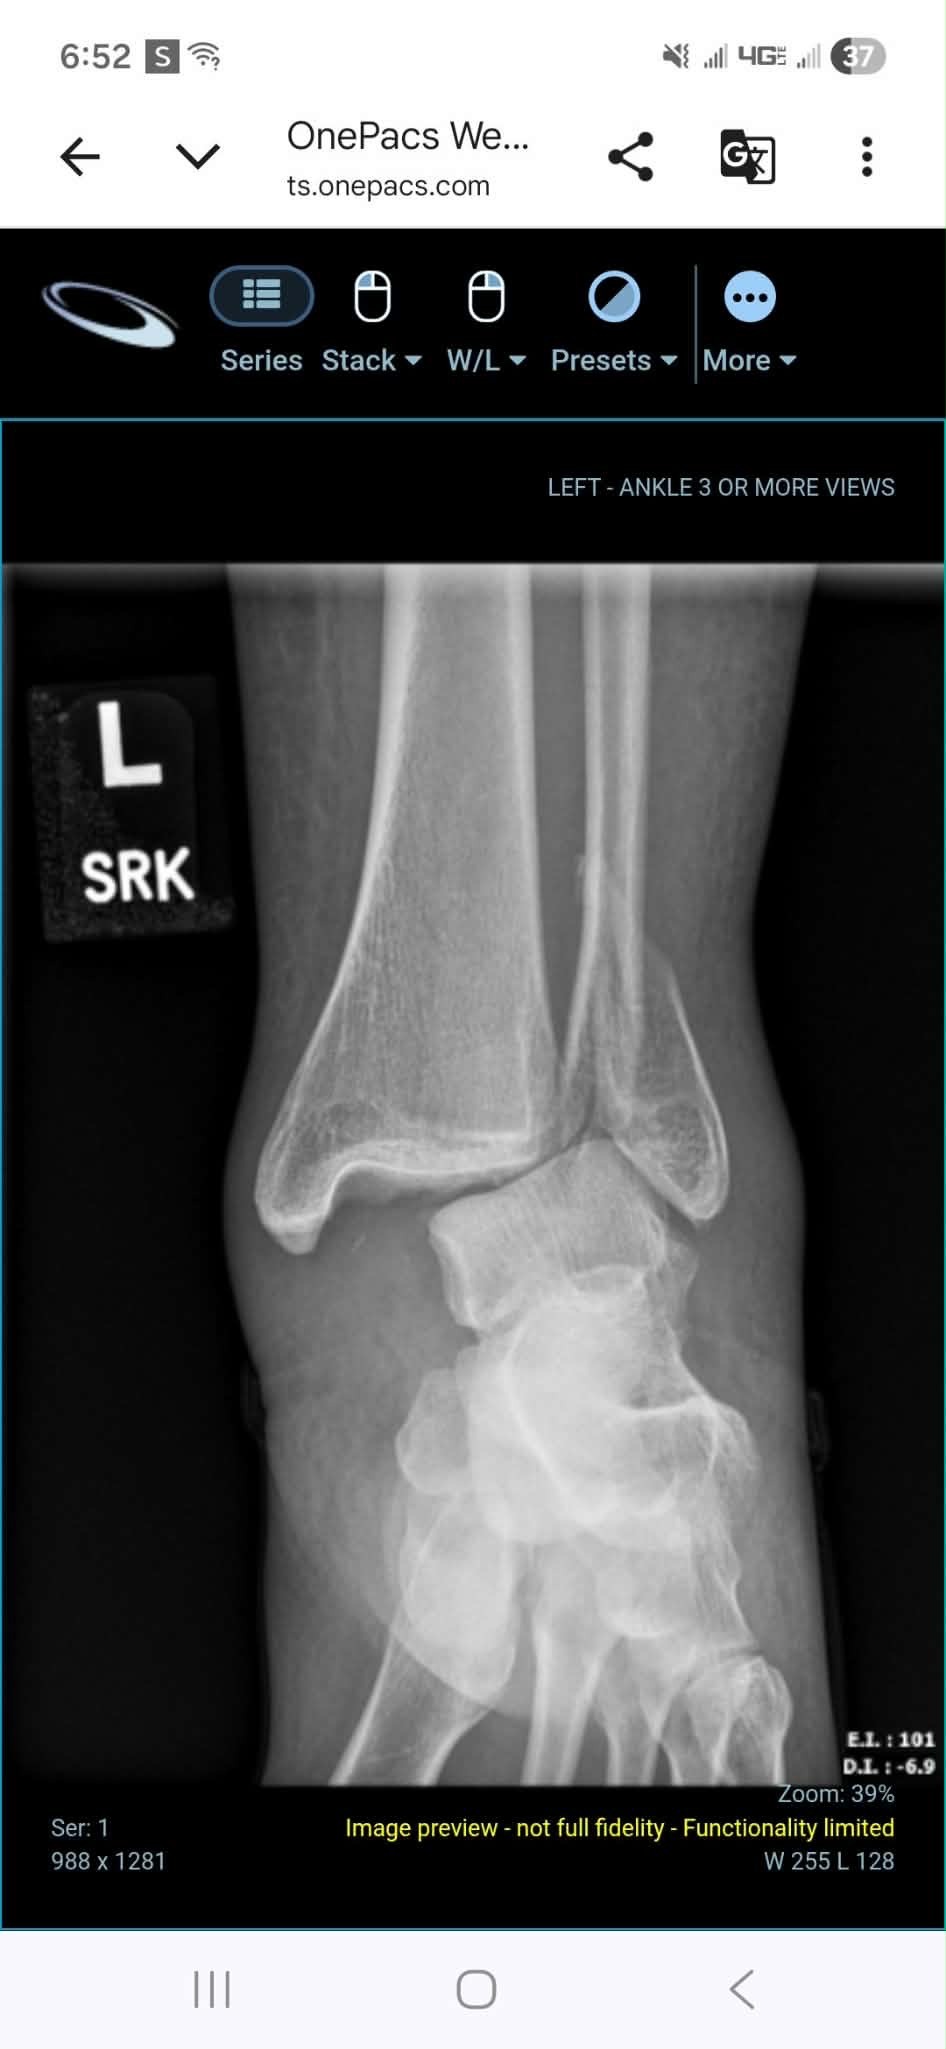

During the first significant snowfall in southern Oregon, Naomi slipped on her front steps and suffered a severe injury—breaking her ankle in multiple places, tearing tendons, and dislocating the joint. She underwent surgery within a week and is now on the long road to recovery. As a mother, it’s heartbreaking to see her in pain and facing so many challenges all at once.